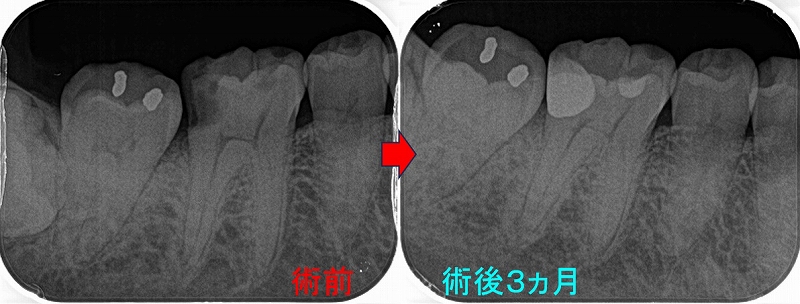

レントゲン

2026 EEdental NAY (1).jpg

第1大臼歯の黄色丸:C2~C3に及ぶ虫歯

第2大臼歯の赤丸:C4に近い虫歯

前に患者さんにも言いましたが、成功率を高くする為には

基本1つ次のステップの治療を行う事

つまり第1大臼歯は神経を取ってクラウン

第2大臼歯は抜歯

こうすることで将来トラブルの出る確率は多少減らせますが、

歯の寿命は確実に短くなりますし、咬みずらくなります。

ここが残りの人生を考えた際の選択になります。

短期予後を取るか!?それとも長い人生・将来的な事を考えた選択をするか!?

前者の難しい歯の保存を説明なしに行うと、上手く行かなかった場合藪医者扱いを受けるので

最初に患者さんにある程度説明を行い理解をしてもらいます。

まず第一大臼歯はいつも通り

とりあえず神経を残す治療を行い、痛みが後で出てしまったら後で神経を取ると説明

2026 EEdental NAY (2).jpg

さて、この第2大臼歯・・・

縁下に大きく虫歯が広がっており、歯に穴を開けずに虫歯をきちんと取るのが超難度

保存をしても歯根破折、咬合から来る虫歯などが怖いのはあり、

将来起こるであろうこのリスクを下げるには抜歯も1つ

患者さんと話し合い、残す方向で治療を行いました。

2026 EEdental NAY (3).jpg

パフォレーションを起こさせないように虫歯を削るのに50分近くかかりましたが、

一応保存治療が行えました。

この先、数カ月様子を見て問題無ければ本歯を作らせてもらいます。